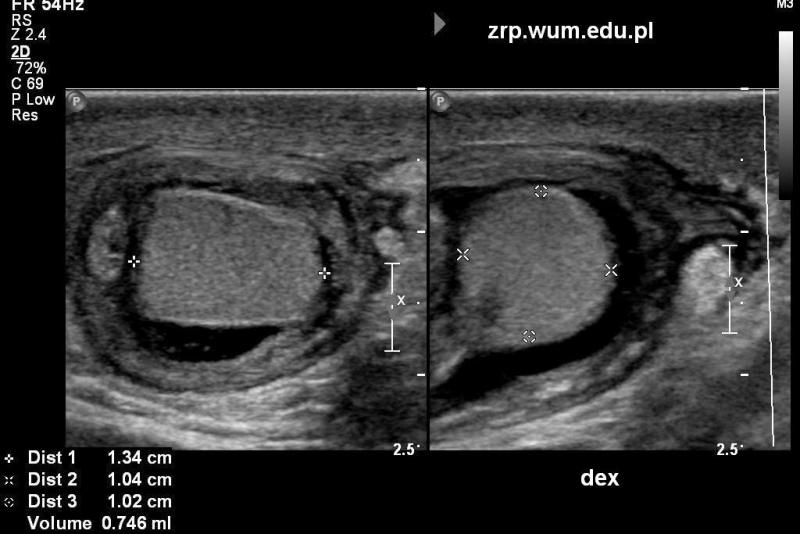

Przypadek 50: 2-miesięczny chłopiec zgłosił się na badanie usg z podejrzeniem przepukliny pachwinowej lewostronnej.

Rozpoznanie: W badaniu usg - uwidoczniono przepuklinę pachwinowę lewostronną - w kanale pachwinowym i w mosznie po stronie lewej widoczne pętle jelitowe (białe strzałki), z zachowaną perystaltyką. Oba jądra widoczne w mosznie, o prawidłowej strukturze i wielkości (czerwona strzałka - jądro prawe, pomarańczowa strzałka - jądro lewe, widoczne poniżej pętli jelitowych).